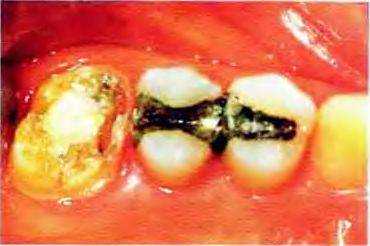

Рис 16-27а. Необходимо заменить старую обширную амальгамную реставрацию

Рис. 16-27Ь. После удаления старой реставрации оказалось, что сохранены достаточный объем и высота твердых тканей, что позволяет восстановить зуб без надстройки культи